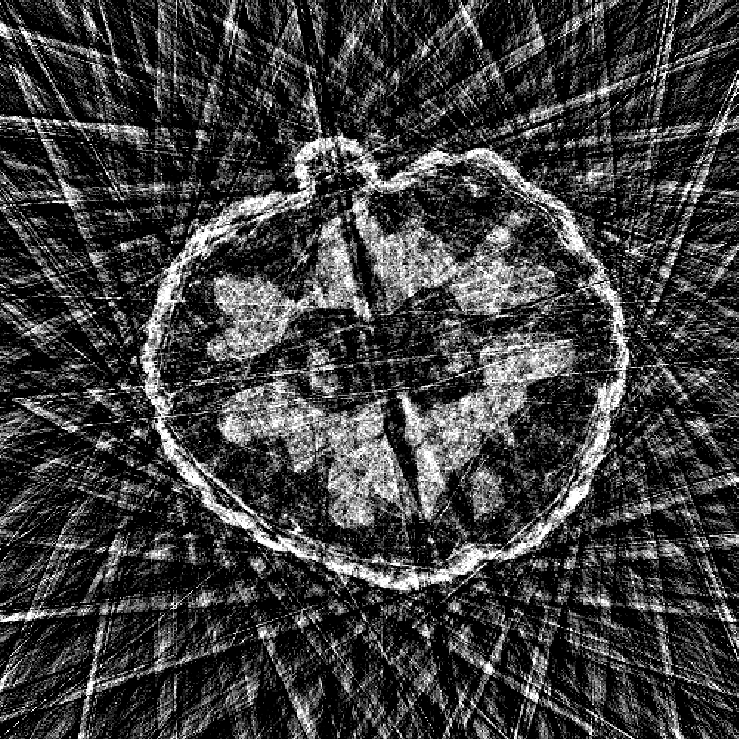

In this work, we find that a good approximation of the normal operator can be obtained by factorizing it as the product of a diagonal matrix and a circulant matrix, which can be efficiently applied using FFTs. This allows us to significantly reduce the computational cost of the data-fidelity step, while maintaining good reconstruction performance. \begin{equation} \label{eq:normal:operator:approximation} \mA^\top \mA \approx \mH = \mathrm{diag}(\vm)^* \mF^{-1} \mathrm{diag}(\bm{\lambda}) \mF \mathrm{diag}(\vm), \end{equation} where $\mF$ and $\mF^{-1}$ are the Fourier and inverse Fourier transforms, respectively, $\vm \in \R^{n}$ is homogeneous to spatial sensitivity map, and $\bm{\lambda} \in \mathbb{C}^{n}$ is the frequency response of the convolution kernel associated with $\mA^\top \mA$.

The parameters $\vm$ and $\bm{\lambda}$ can be learned end-to-end by minimizing the loss \begin{align} \mathcal{L}(\vm, \bm{\lambda}) &= \E_{\rvx \sim \mathcal{N}(\bm{0}, \mI)} \| \mA^\top \mA \rvx - \mH(\vm, \bm{\lambda}) \rvx \|_2^2 \notag\\ &= \| \mA^\top \mA - \mH(\vm, \bm{\lambda}) \|_F^2 \label{eq:frobenius:loss} \end{align}

Illustrations of the normal operator approximation on the Walnut-CBCT dataset. (top row) Original volume slice $\vx$, exact normal operator evaluation $\mA^\top \mA \vx$, and approximated normal operator $\mH\vx$. (bottom row) Learned filter $\bm{\lambda}$, learned mask $\vm$, and squared approximation error $(\mA^\top \mA \vx - \mH \vx)^2$.

Now we can use the approximation $\mH$ instead of the exact normal operator $\mA^\top \mA$ in the partitioned data-fidelity step \eqref{eq:data:step:partitioned}. The factorization $\mH$ admits an efficient evaluation on a small patch by restricting the size of underlying convolution kernel, and by cropping the spatial mask $\vm$ to the patch size.